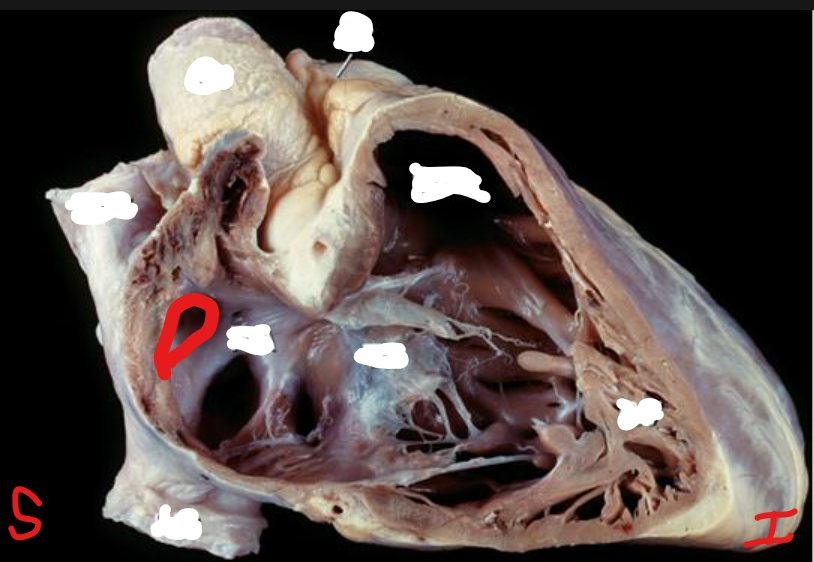

Name the valve and list the components of the valve

Aortic Semilunar Valve

nodule